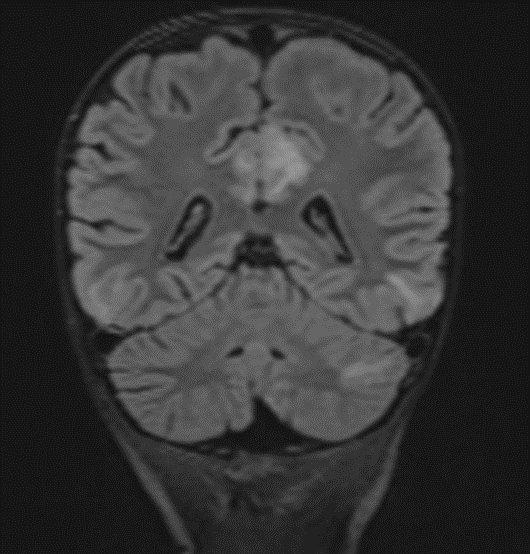

Subsequently, an MRI of the brain was performed, which demonstrated: Bilateral diffuse high signal changes in the cerebellum on T2 and FLAIR sequences, as well as areas of restricted diffusion, indicating focal zones of cytotoxic edema.

Picture 2.

The MRI of the brain revealed the following findings:

- Bilateral subcortical zones, predominantly in the occipital region, exhibiting confluent hyperintense signals on T2 and FLAIR sequences, accompanied by edema.

- A suspected area of cytotoxic edema in the superior parietal lobe.

- High signal intensities on T2 and FLAIR sequences observed in the centrum semiovale, right of the corpus callosum body, and bilaterally in the frontal gyrus, without diffusion restriction.

- In the supraventricular region, extending inferiorly from the projection of the postcentral gyrus into the subcortical white matter to the posterior part of the corpus callosum body (excluding it), and in the left superior temporal lobe, there was a cortico-subcortical lesion characterized by cytotoxic edema and restricted diffusion.

Bilateral Occipital Dominant Subcortical Hyperintense Zones: These areas were evident on T2-weighted and FLAIR sequences, indicating diffuse cerebral involvement. The predilection for the occipital region was consistent with reported cases of MTX-LE, which often presents with symmetric white matter changes.

Edema and Cytotoxic Edema: The superior parietal lobes showed suspected zones of cytotoxic edema. This was further supported by the presence of diffusion-weighted imaging (DWI) changes, characterized by restricted diffusion, a hallmark of cytotoxic edema. These findings align with the pathophysiology of MTX-LE, where MTX-induced neuronal damage leads to cellular swelling and subsequent restricted diffusion.

Supraventricular and Frontal Gyrus Involvement: High signal intensities on T2 and FLAIR sequences were noted in the centrum semiovale, right of the corpus callosum body, and bilaterally in the frontal gyrus, without diffusion restriction. This suggests early involvement before the development of significant cytotoxic damage.

Cortico-Subcortical Lesion in the Left Superior Temporal Lobe: This region exhibited cytotoxic edema with restricted diffusion, underscoring the multifocal nature of MTX-LE. The involvement of both cortical and subcortical areas is a typical feature in severe cases of MTX-LE.